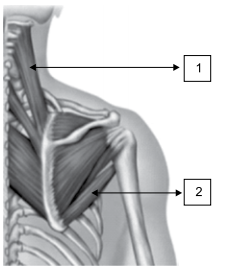

Assinale a alternativa que corretamente identifica os músculos dos membros superiores.